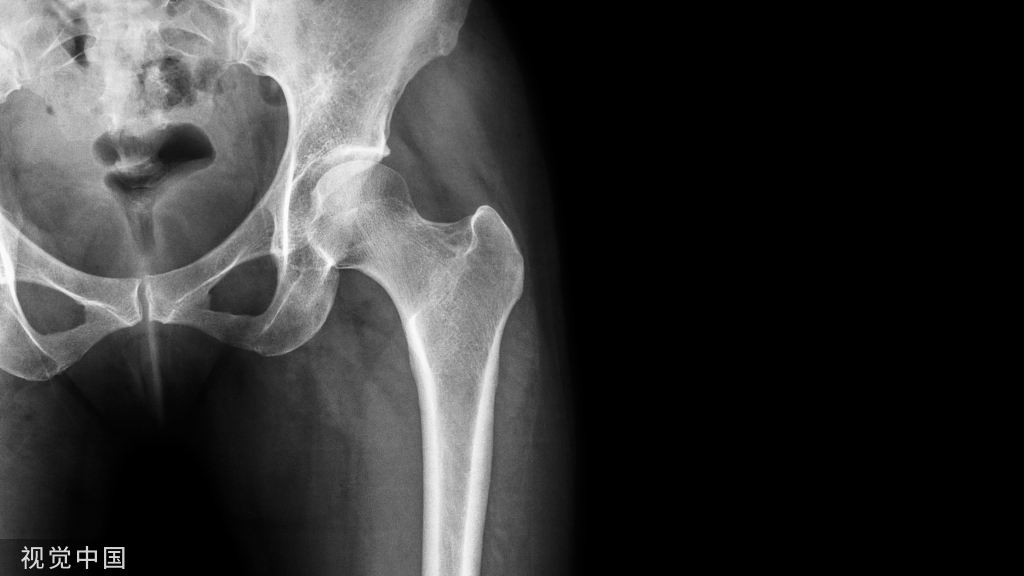

根据肱骨头脱位的方向可分为前脱位、后脱位、上脱位及下脱位四型,以前脱位最多见。由于暴力的大小、力作用的方向以及肌肉的牵拉,前脱位时,肱骨头可能位于锁骨下、喙突下、肩前方及关节盂下。

有上肢外展外旋或后伸着地受伤史;肩部疼痛、肿胀、肩关节活动障碍,以健手托住患侧前臂;方肩畸形,肩胛盂处有空虚感,上肢有弹性固定;搭肩试验阳性(Dugas征);直尺试验阳性;测量肩峰到肱骨外上髁长度;X线正位、侧位片及穿胸位片可确定肩关节脱位的类型、移位方向及有无撕脱骨折。